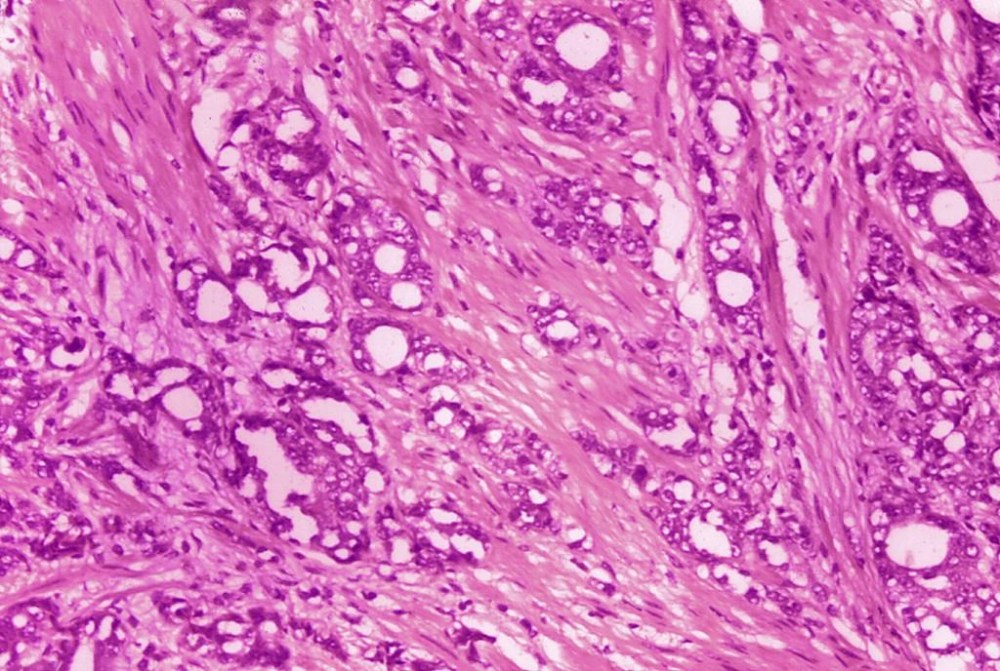

Researchers have found long-term evidence that actively monitoring localized prostate cancer is a safe alternative to immediate surgery or radiation.

The study directly compared the three approaches — surgery to remove tumors, radiation treatment and monitoring. Most prostate cancer grows slowly, so it takes many years to look at the disease’s outcomes.

Researchers followed more than 1,600 U.K. men who agreed to be randomly assigned to get surgery, radiation or active monitoring. The patients’ cancer was confined to the prostate, a walnut-sized gland that’s part of the reproductive system. Men in the monitoring group had regular blood tests and some went on to have surgery or radiation.